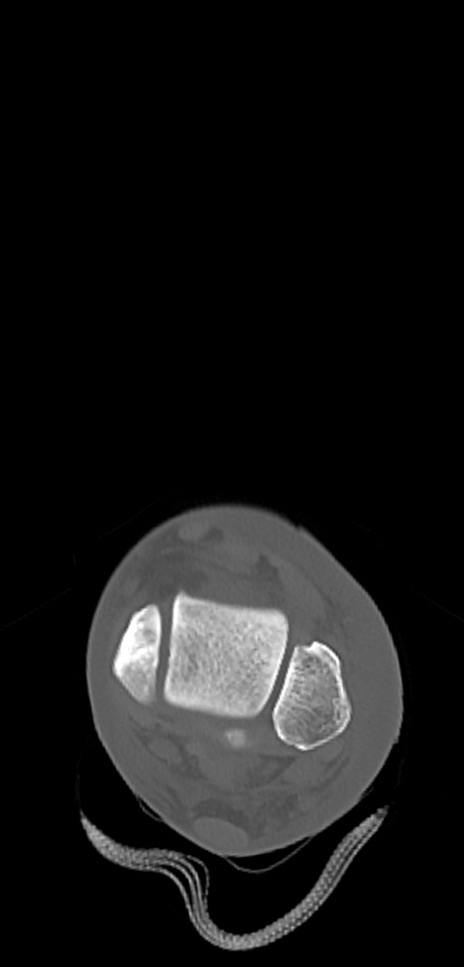

症例37 左足関節CT(横断像)

左足関節CT